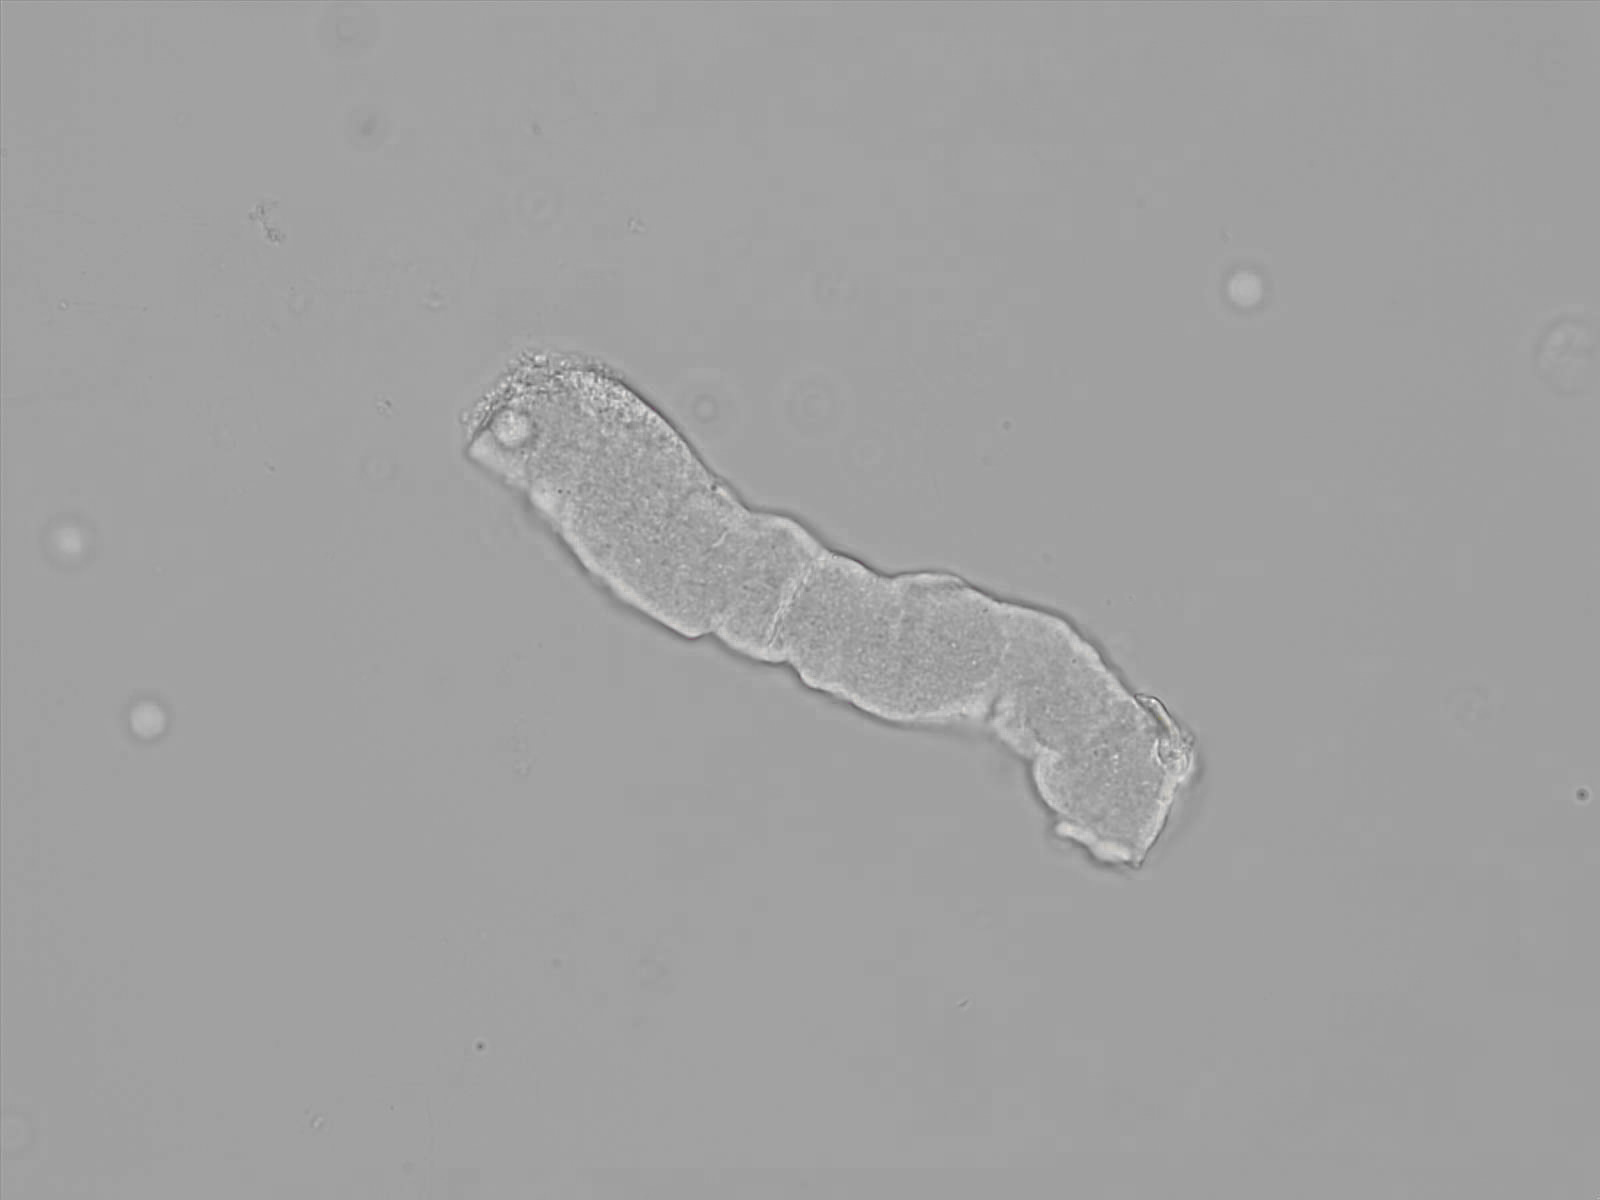

what

Hyaline Cast

Hyaline significance

Strenuous exercise, stress, dehydration, glomerulonephritis, pyelonephritis, chronic renal disease

this is:

RBC cast

Significance of RBC cast

Bleeding in the nephron

(acute glomerulonephritis, lupus nephritis, pyelonephritis, strenuous exercise) verify with positive blood on reagent strip + free standing RBCs on slide

what this

WBC cast

this is what

Waxy cast